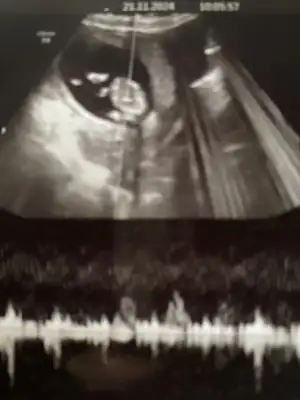

Evet bende sabahları uyanınca belimde batma oluyor geceleri farkında olmadan yattığımdan dolayı sanırım. Ama gündüz plasenta previa durumumdan dolayı hep yatmak zorundayım onda da rahimde çekilme varmış gibi hissediyorum sola veya sağa döndüğümde rahatım.Ben 12.haftadan beri sirt ustu yatarsam belim agriyor. Dun gece de hatta nasil olduysa donmusum yine sirt ustu. Sabah kendimi sirt ustu yatarken buldum ve acaip bi bel agrim vardi. Sonra biraz hareket edince gecti neyse ki.